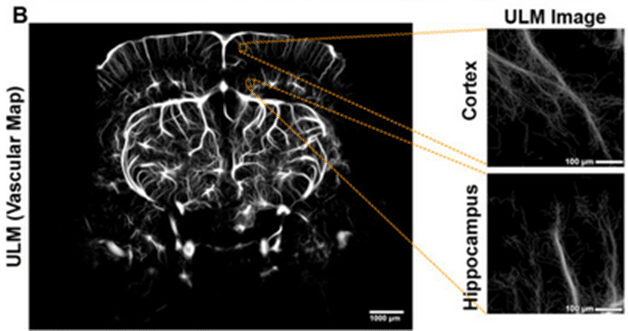

In a supplementary part of the study, the authors used the microbubble-enabled ultrasound localization microscopy (ULM) technique with Iconeus One to enhance the imaging contrast still further and enable high-resolution mapping of the vascular density. They also carried out a comparison against data acquired using post-mortem immunofluorescence imaging of the vasculature, again finding a strong positive correlation (Pearson r = +0.82).

Representative ULM vascular map (left), and representative 500 µm2 sampled regions used for comparison with LSCI (right).